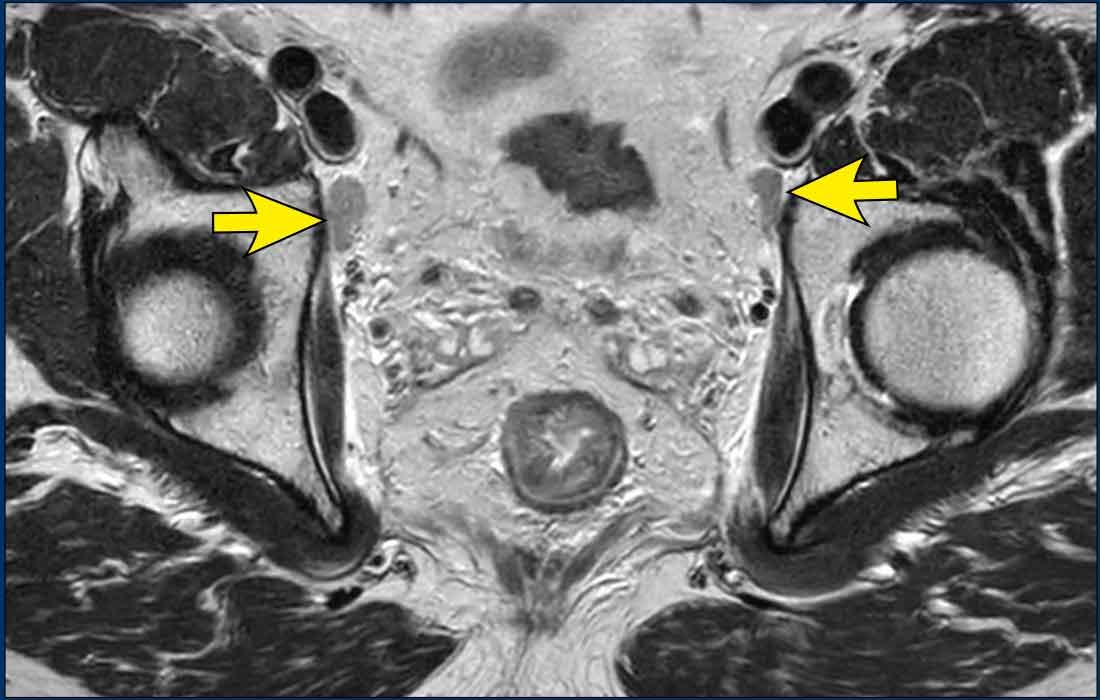

Hạch bạch huyết bên (chậu trong/bịt)

Các hạch bạch huyết chậu trong và bịt bên chủ yếu được đánh giá theo kích thước, với ≥7 mm (trục ngắn) là tiêu chí chính cho cN+.

Đặc điểm hình thái học—ranh giới không rõ ràng,

tín hiệu không đồng nhất, hình dạng tròn và mất rốn mỡ—có thể hỗ trợ

chẩn đoán ác tính trong các hạch kích thước trung bình (5–7 mm), đặc biệt nếu có nhiều hạch hoặc

khi có sự hiện diện của các hạch bên rõ ràng bệnh lý khác.

Yêu cầu Báo cáo

Bất kỳ hạch N+ bên nào (dù đã được gộp vào phân loại cN chung) đều phải được nêu bật riêng trong báo cáo MRI, với vị trí và kích thước được chỉ định cụ thể, vì những hạch này cần được điều trị có mục tiêu để ngăn ngừa tái phát bên.

Hình ảnh

- Hình ảnh bên trái: Hạch bạch huyết bệnh lý 9 mm ở khoang bịt bên trái (mũi tên), được xác định tại thời điểm phân loại giai đoạn ban đầu. Cần xạ trị và/hoặc cắt bỏ riêng biệt để tránh tái phát bên ngoài.

- Hình ảnh bên phải: Bệnh nhân được điều trị bằng phương pháp TME tiêu chuẩn (không cắt hạch bên) đã xuất hiện khối u không đều ở khoang bịt trái, phù hợp với tái phát hạch bên.